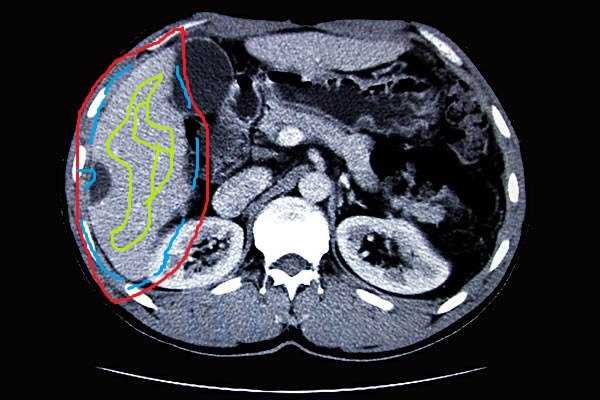

这个不是本回答的重点,只说两句。师兄说要像上图那样标出目标器官大致区域和前后景区域,然后用openCV里的GrabCut来把目标区域挖出来,这样精度会相对高一点。把目标区域挖出来以后就对图像二值化再保存成文件,属于肝的像素是1,背景是0。!!!!!!!!然后这个才是重点!!!!!!!!!!

这个不是本回答的重点,只说两句。师兄说要像上图那样标出目标器官大致区域和前后景区域,然后用openCV里的GrabCut来把目标区域挖出来,这样精度会相对高一点。把目标区域挖出来以后就对图像二值化再保存成文件,属于肝的像素是1,背景是0。!!!!!!!!然后这个才是重点!!!!!!!!!!